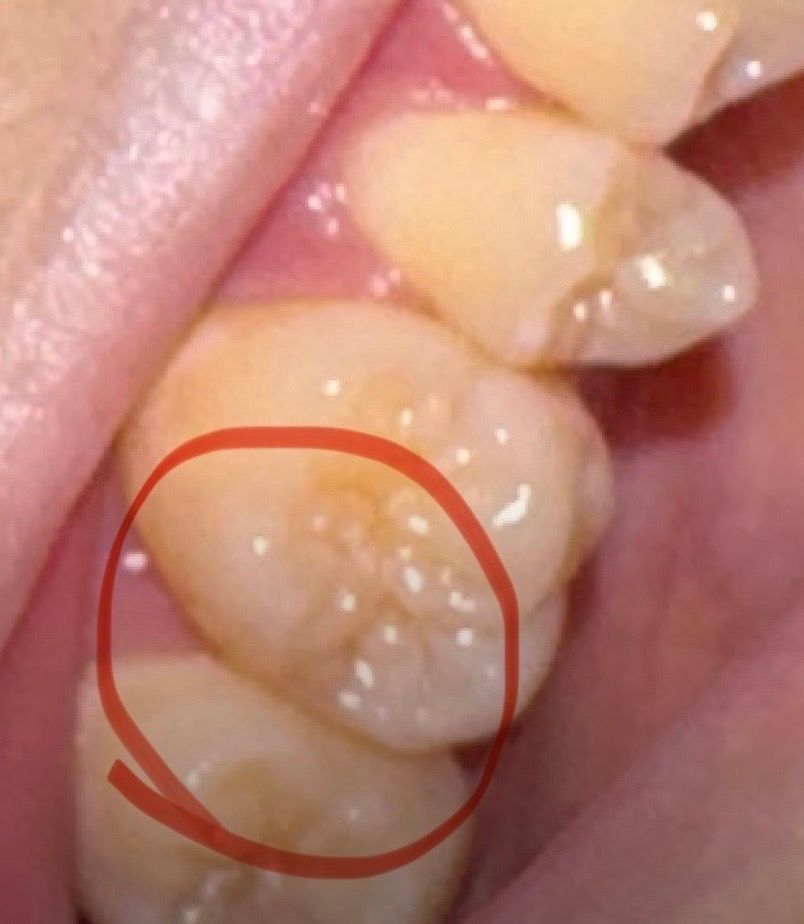

사진 속 치아가 불편한데 충치일 가능성이 있나요?

어제부터 음식 먹는데 아픈 것도 아니고 간지러운 것도 아 니고 뭔가 오묘하게 불편한 느낌이 들더군요 아주 미세한데 제가 예민해서 알아차렸어요 요새 많이 피곤하고 잠도 잘 못자서 예민해져 쓸데없이 잘 느끼는 건지 아니면 그냥 충치인지 모르겠네요 현재 일이 많아 치과를 갈 시간을 낼 수가 없는데 의사선생 님들께서 보시기엔 충치라고 생각하시나요?

그리고 치과를 못 가는 상황인데 호전되거나 더 심해지지 않게하는 법 있나요?

충치가 보이지는 않습니다. 내부에 있을 수도 있으니 증상 지속시엔 치과 가보시는 게 좋습니다.

사진이 흐려 정확하지 않습니다. 다만 충치가 약간 표면만 있거나 아예 충치가 아닐 가능성이 있습니다. 지금 당장 급한 것은 아니니 시간날 때 치과에 가서 검사 받으세요.

육안상으로는 충치가 있어 보이진 않지만, 불편하시면 치과에 가셔서 일단 엑스레이를 찍어보시는게 좋을것같습니다.

1. 충치가 아닐 가능성이 높습니다.

2. 차갑거나 뜨거운 음식등에 확실하게 민감한 반응을 보이는게 아니라 우리우리하게 아픈거라면 잇몸 문제일 가능성도 있을 것 같습니다.

3. 일단 양치질 할 때 바스법으로 하여 잇몸 마사지를 해보시고 증상개선여부를 보시기 바랍니다.